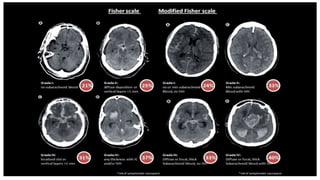

Fisher grading scale (amount of blood on CT

scan is a predictor of vasospasm)

Fisher grading scale(amount of blood on CT scan is a predictor of vasospasm)